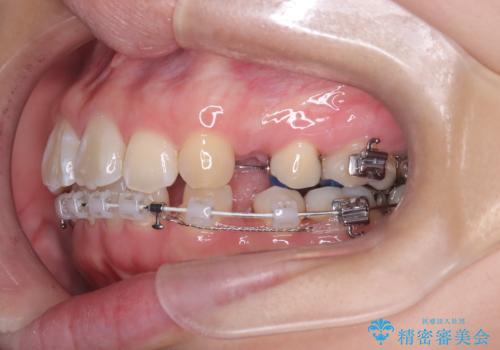

- 口元が出ている(突出している)ことを気にされて来院されました。精密な検査の結果、前歯を大きく後退させるスペースが必要と診断。患者様の**「前歯を下げたい」という強いご要望に応えるため、上下左右の第一小臼歯を抜歯し、そのスペースを利用して前歯を奥へ移動させる治療計画を立案しました。また、人目を気にせず治療できるよう、上顎に裏側矯正、下顎に表側矯正を組み合わせたハーフリンガル矯正**を提案しました。

今回の矯正治療では、前歯を大きく後退させるスペースを確保するため、計画通り上下左右の第一小臼歯を抜歯しました。装置には、上顎には目立たない裏側矯正(舌側矯正)を、下顎には透明な審美ブラケットを使用するハーフリンガル矯正を採用しました。抜歯によってできたスペースを最大限に活用し、前歯を効率よく後方へ移動。治療の結果、口元の突出感が大幅に解消され、Eライン(横顔の美しさの基準)も改善しました。人目を気にすることなく治療を完遂し、自信の持てる美しい横顔を獲得していただけました。